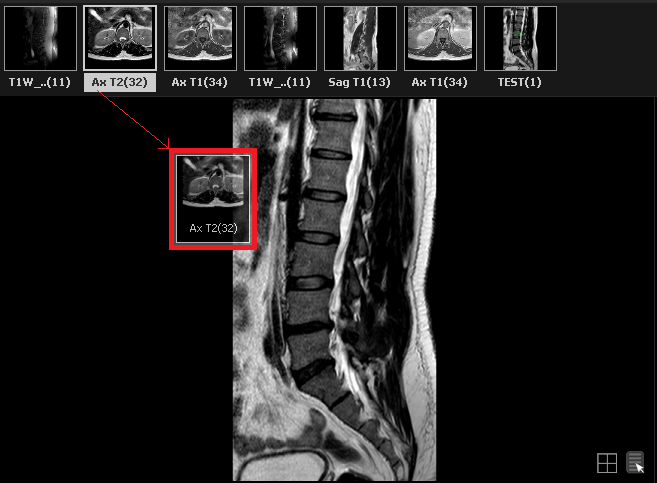

» To display a series in one of the windows, the user must drag the series from the series panel into an image window as shown below: